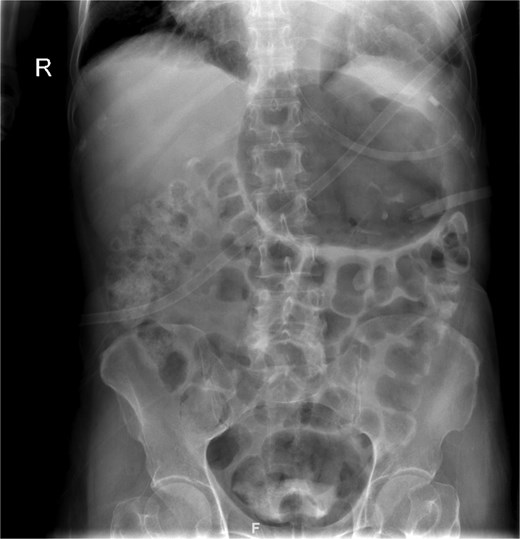

The patient was admitted under the care of the general surgery department, and he was taken to the operating room for a laparoscopic exploration, which showed mesenteroaxial gastric volvulus, wandering spleen, and a large hiatal hernia which was ~5 cm in size. No devitalized tissues were found. An attempt at intraoperative endoscopy failed to pass through the hiatus. A cruroplasty with a Toupet fundoplication and gastropexy were done as shown in (Figs 3 and 4). On the third postoperative day, the patient was doing well. He was tolerating oral intake and passing regular motions and was discharged home in good condition as he was traveling to his country.

(a) The spleen appears healthy and in an abnormally mobile position, consistent with a wandering spleen, with absent or lax ligamentous attachments. (b) Postreduction view of the stomach, with its body sutured to the lateral abdominal wall (gastropexy) to prevent recurrence of mesenteroaxial gastric volvulus.